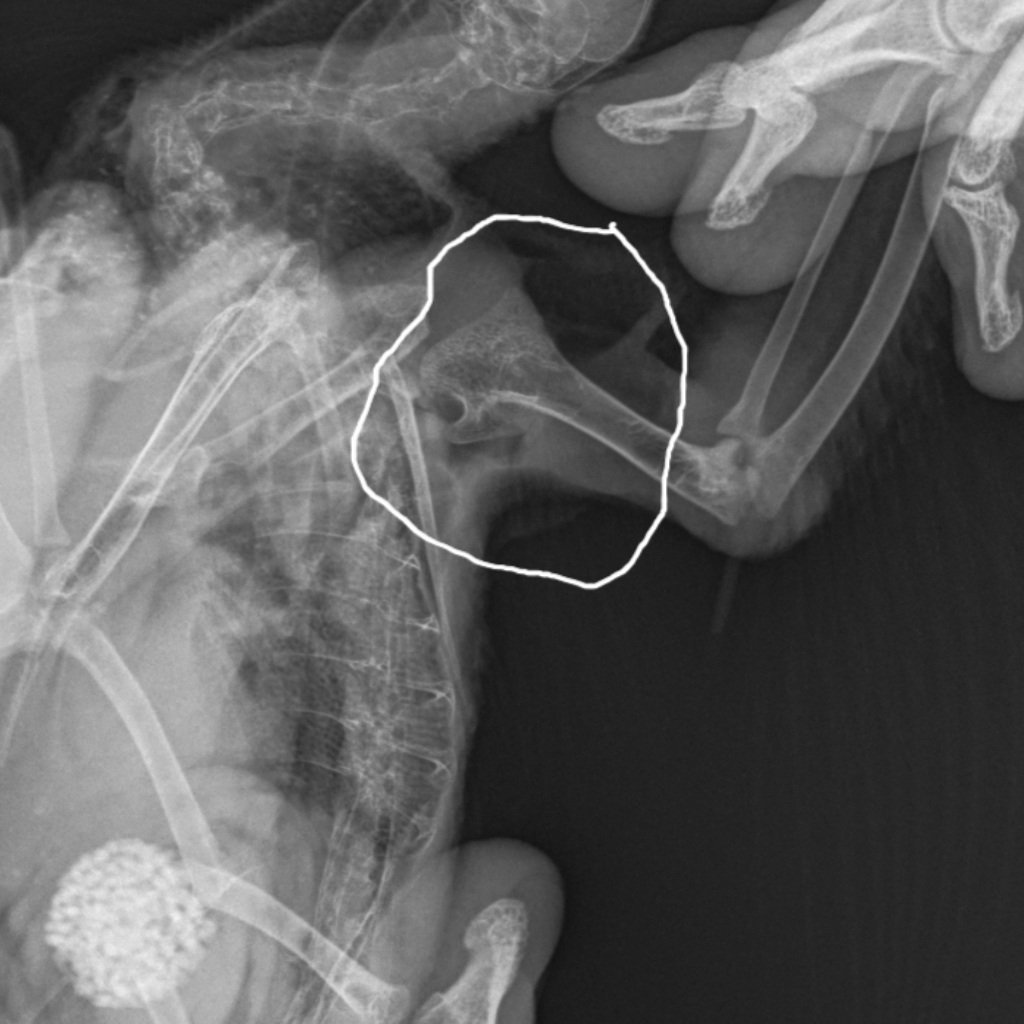

@маленький принцрентген получился только так,держал один,где обведено место опухоли,второй снимок здоровое крыло

Скелет Мелкий  _ 10 kg-Плечо LAT-05.03.2024-14_32_40-240.JPEG

Скелет Мелкий  _ 10 kg-Плечо LAT-05.03.2024-14_32_39-865.JPEG